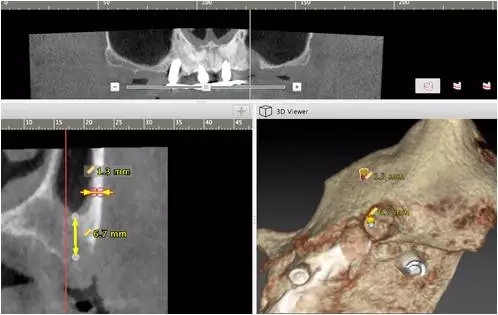

10個(gè)月后出現(xiàn)左上頜咬合痛,X線檢查發(fā)現(xiàn)上頜左側(cè)前磨牙區(qū)傾斜種植體周圍低密度影,臨床檢查種植體松動(dòng),其余種植體骨結(jié)合良好,遂拔除該種植體(圖3-4)。愈合3個(gè)月,CBCT片顯示:25區(qū)種植窩空虛(圖5),愈合不佳,26區(qū)竇底剩余骨高度不足2mm(圖6),其余種植體骨愈合良好,15區(qū)傾斜種植體邊緣骨疑似吸收至第三螺紋(結(jié)合全景片)?;颊咭蠊潭ㄐ迯?fù)。

圖5

圖6

2、增加上頜種植體數(shù)量,分別與16、25、26植入3顆,行6顆種植體支撐的常規(guī)種植固定義齒修復(fù)(圖7)。16、25、26區(qū)剩余骨高度嚴(yán)重不足是該方案的不利方面,存在因需要上頜竇底提升手術(shù)所帶來(lái)的相應(yīng)手術(shù)風(fēng)險(xiǎn)。但是,上頜竇底提升術(shù)是一個(gè)成熟、可靠的技術(shù)方法,經(jīng)過(guò)與患者充分溝通,最終選擇了這一方案。